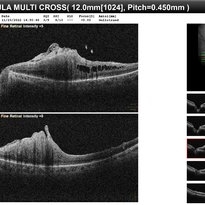

RPE rip in a case of Idiopathic polypoidal choroidopathy RPE rip in a case of Idiopathic polypoidal choroidopathyOct 23 2022 by Anjana Mirajkar, MS Ophthalmology OCT image in a of 61 year old male with RPE rip in a case of Idiopathic Polypoidal Choroidopathy. Photographer: Dr. Anjana Mirajkar -Retina Foundation, Ahmedabad Condition/keywords: Idiopathic polypoidal choroidopathy, RPE rip